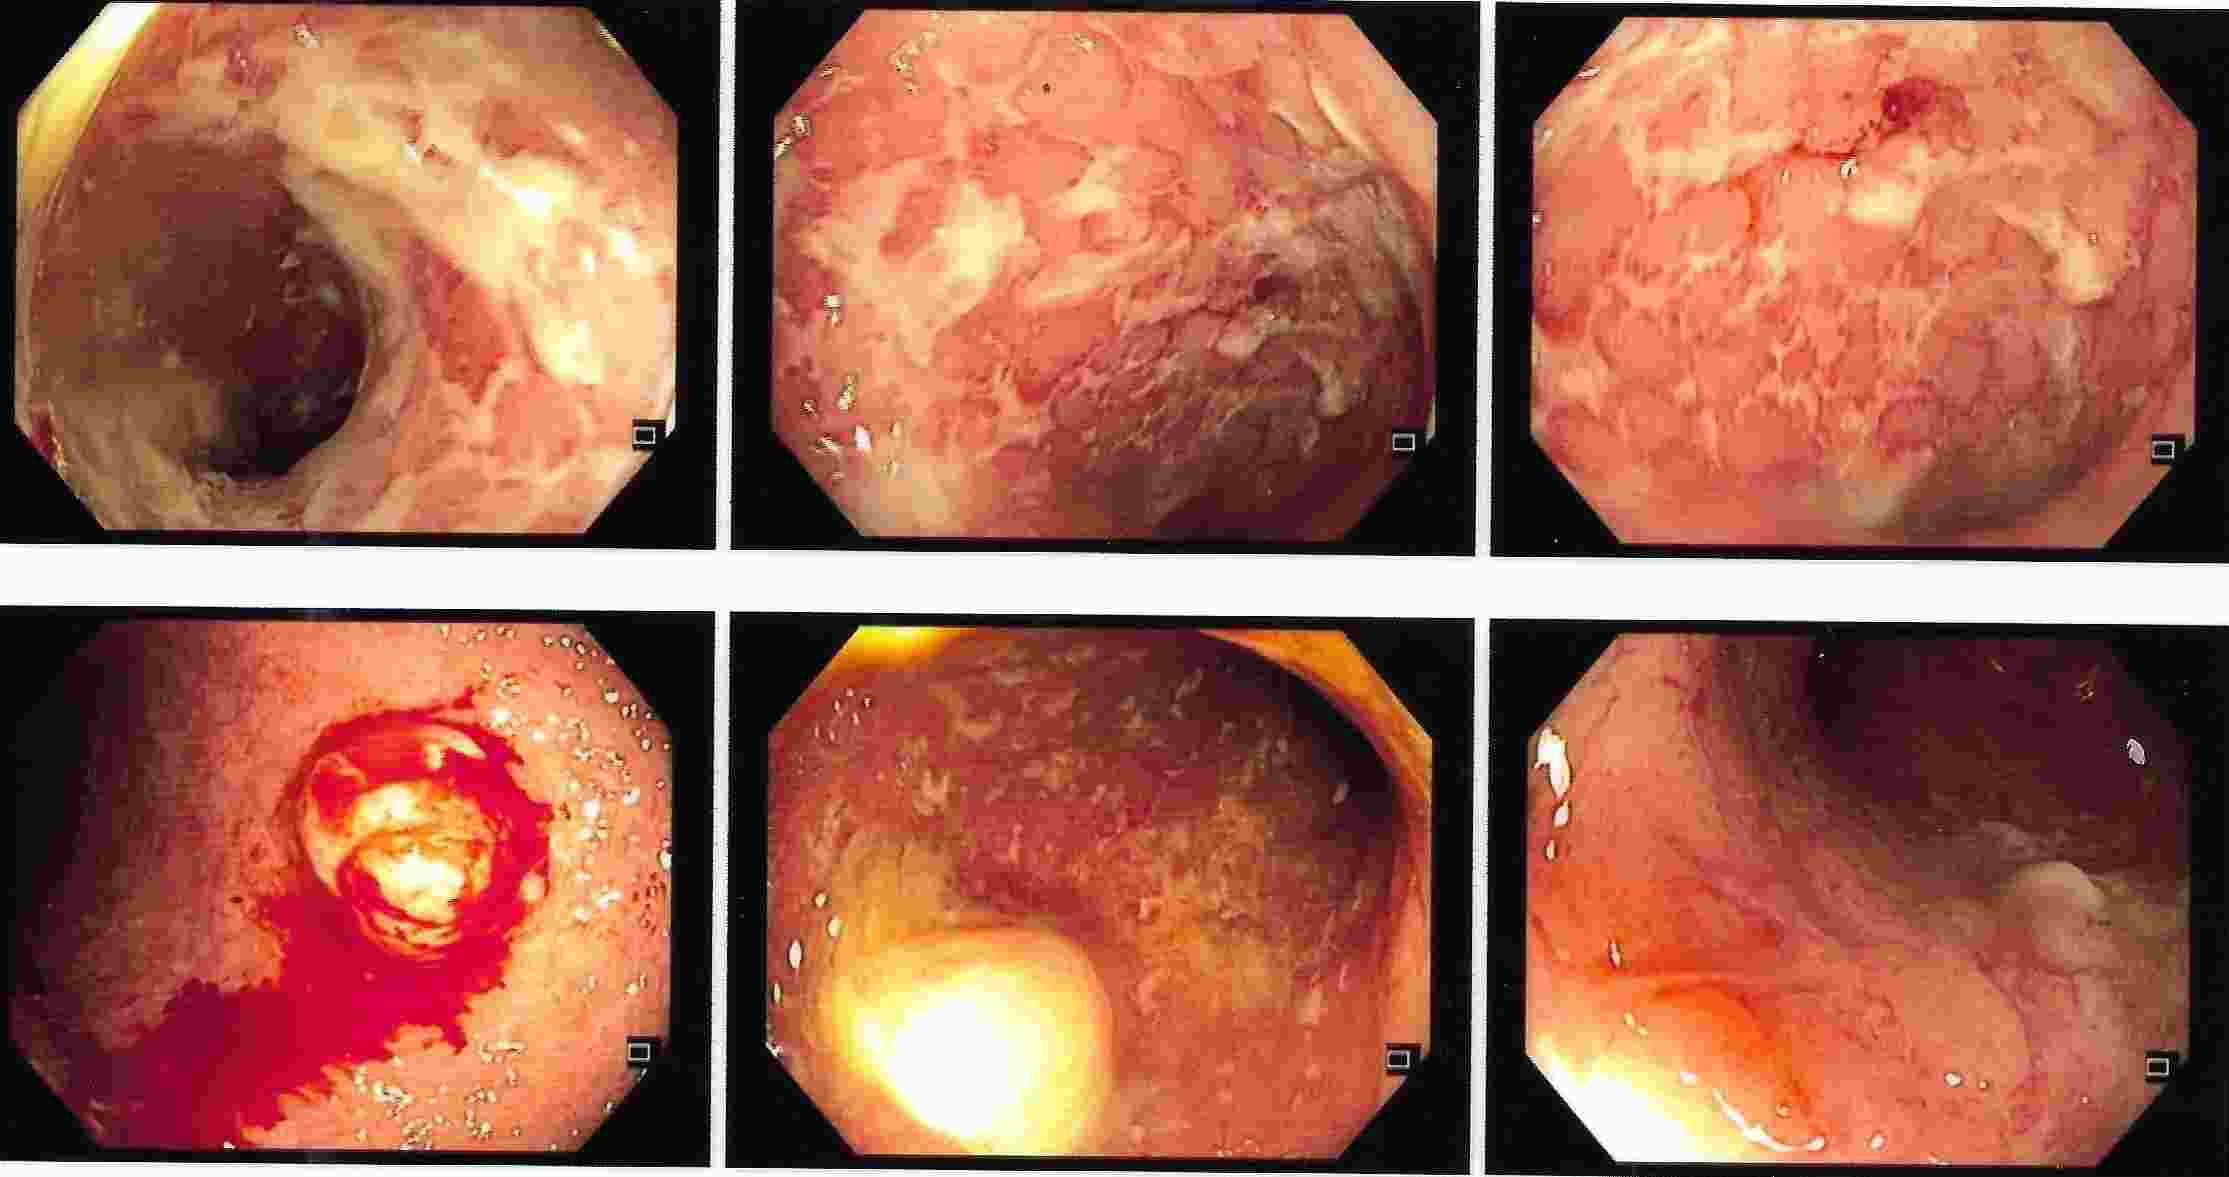

Altered bowel habits, watery or semisolid stools, gripping pain in abdomen, mucus and blood in the stool,

incomplete evacuation can all be due to a condition called as colitis. Colitis has got different causes

like ulcerative colitis, Crohn’s disease, infections, tuberculosis, amoebic colitis, bacillary dysentery and many more.

Corrcet diagnosis by Colonoscopy will allow patients to be treated properly.

IBD - Ulcerative Colitis

IBD - Crohn's Disease

Ulcerative Colitis

Ulcerative Colitis

Crohn's Disease